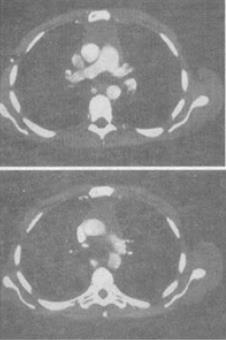

- 单项选择题 患者男,64岁,胸部隐痛伴眼睑下垂2个月余,结合影像学检查,最可能的诊断是()。

B、胸腺瘤

- B